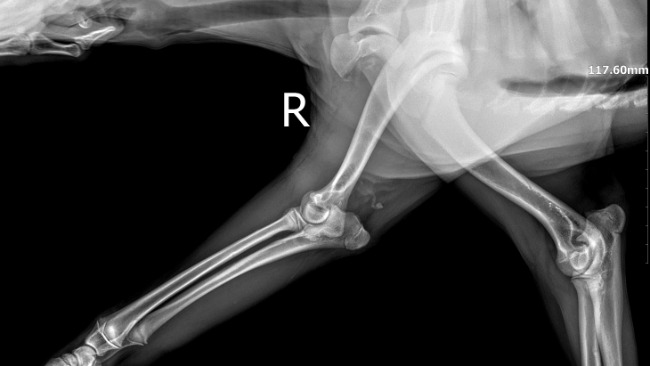

Harry to młodziutki (ok.1 roku) wyżełek po wypadku komunikacyjnym, w którym ucierpiały jego łapki. Łapka przednia wymaga natychmiastowej interwencji chirurgicznej!!!

Edit : W lecznicy podjęto decyzję o operowaniu obydwu łapek, koszt 3000 zł!!!

Dołączam zdjęcia rtg łapek, które ucierpiały oraz opis z lecznicy.